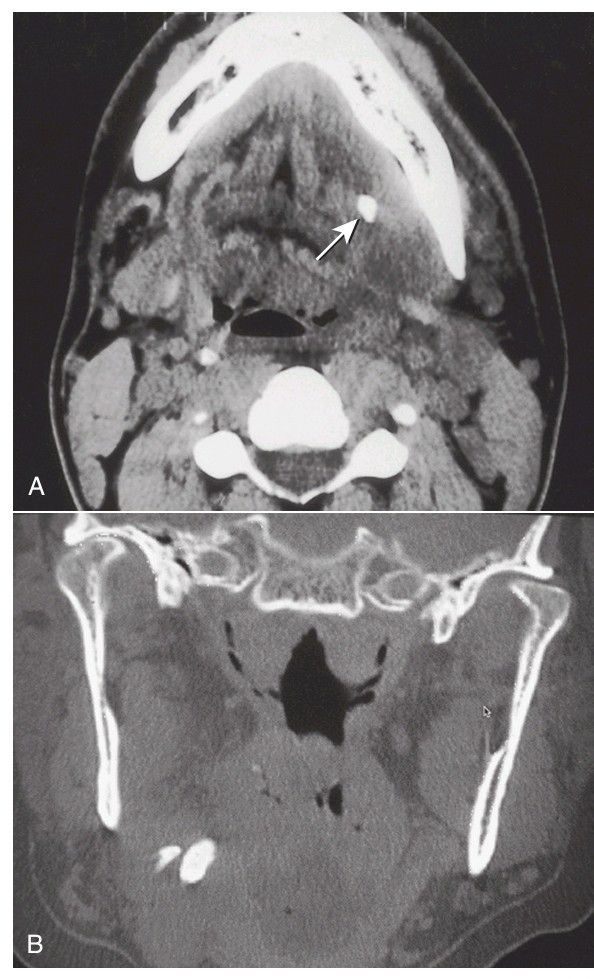

A) Axial computed tomography (CT) scan of the mandible and floor of mouth shows a posterior submandibular sialolith (arrow). (B) Coronal CT scan showing a two stones in the submandibular duct near the gland hilum.